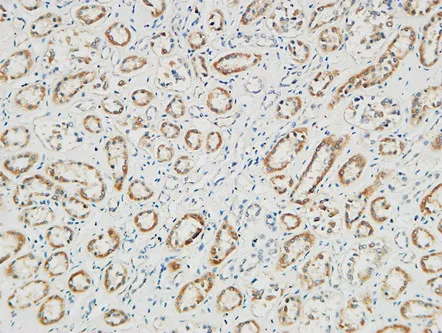

Ribosomal Protein S6 Rabbit Polyclonal Antibody

Cat: APRab17189

Size1:50μl Price1:$118

Size2:100μl Price2:$220

Size3:500μl Price3:$980